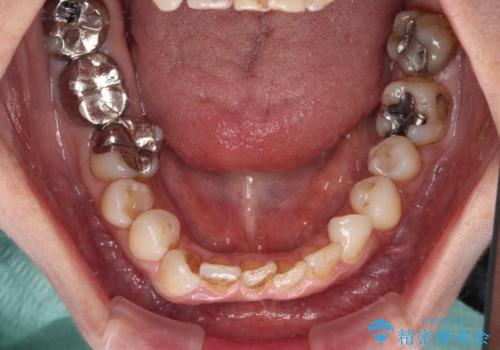

- 上下前歯のデコボコと、治療途中の歯を気にして来院された患者様です。

根管治療が必要な歯は事前に処置を行った上で矯正治療を開始し、概ね歯列が整ったところでセラミッククラウンなどに置き換え、その後インビザラインを1セット使用して仕上げていくこととしました。